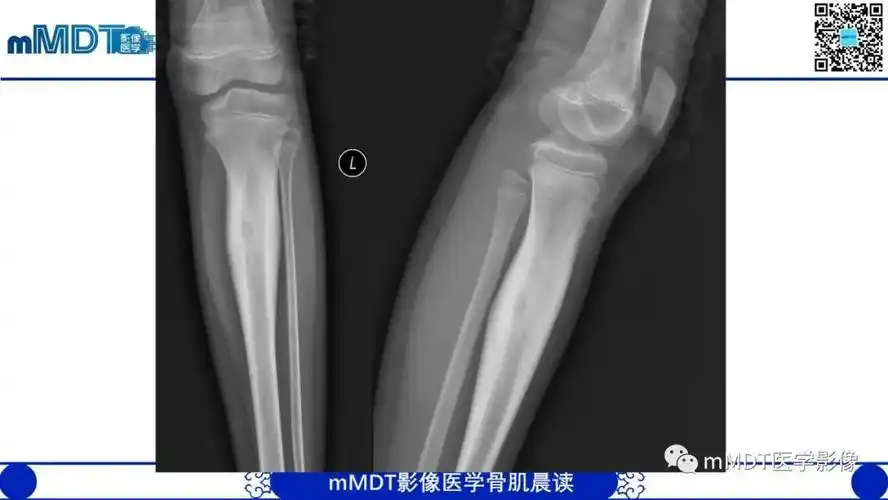

骨旁骨肉瘤影像诊断